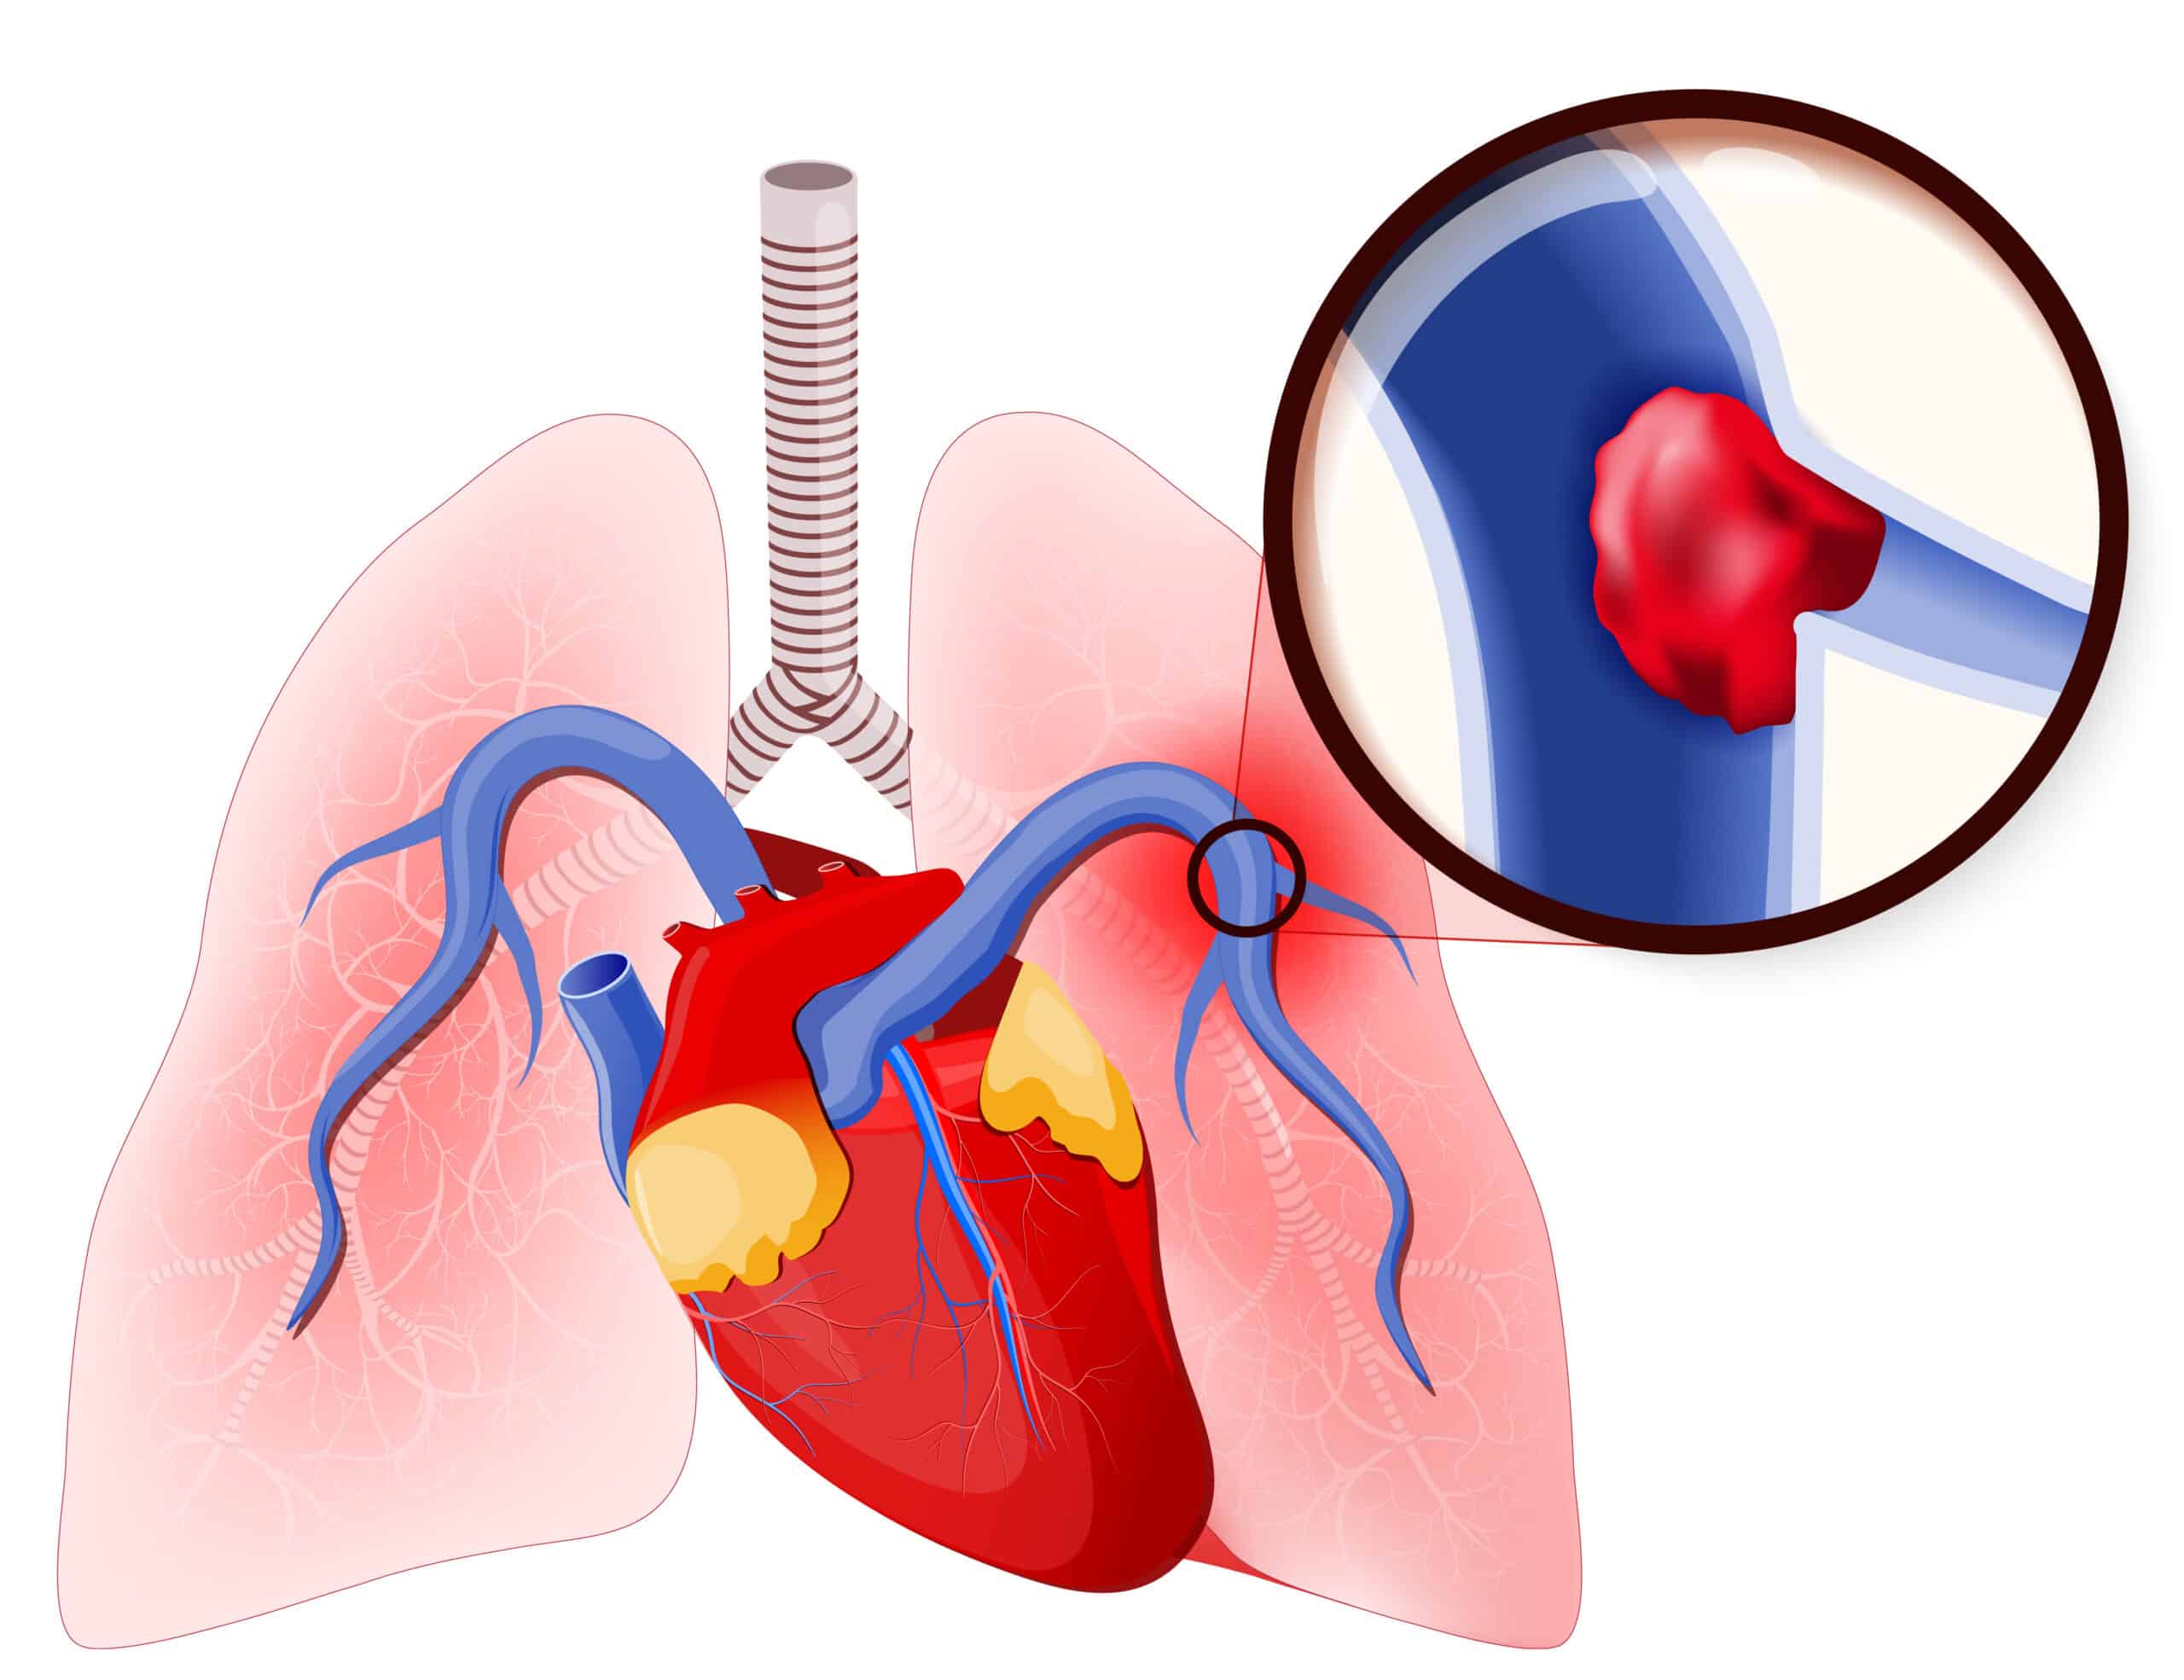

Pulmonary thrombosis, also known as a pulmonary embolus (PE), is a cause of cardiac arrest and shock. The sudden obstruction of the pulmonary vasculature leads to an increase in right heart pressures and vasoactive factors that can cause cardiac shock and eventual arrest. Severe or fulminant PE is the most likely cause of cardiac arrest and occurs in about 5% of patients. This severe disease has a high mortality rate of between 65% and 90%. Progression to cardiac arrest can occur within a few hours. Due to the often severe symptoms, patients will usually seek medical care. Patients may have risk factors for thrombosis (e.g., cancer, recent surgery), shortness of breath, and a sudden witnessed arrest. The majority of PE-associated cardiac arrests (36–53%) will present with PEA.

Pulmonary Embolism

Treatment of fulminant PE includes embolectomy (percutaneous or surgical), systemic thrombolysis, and extracorporeal CPR as routine anticoagulation is not sufficient to resolve a massive clot.

When a patient has cardiac arrest due to a known PE, there are several options for therapy. These include surgical or mechanical embolectomy and systemic thrombolysis. No one therapy is recommended over others, but rather the best option depends on the patient’s circumstances, the provider’s skillset, and the therapies locally available. Thrombolysis may still be used even in a patient who has received chest compressions and other relative contraindications due to the poor survival outcomes from fulminant PE.

When a patient has suspected PE causing cardiac arrest, thrombolysis can be offered. However, there are no consensus data regarding the criteria for suspected PE nor the recommended dosing, medication, or timing of thrombolytic treatment. Currently, there is no good research regarding the use of surgical or mechanical embolectomy in this patient group.